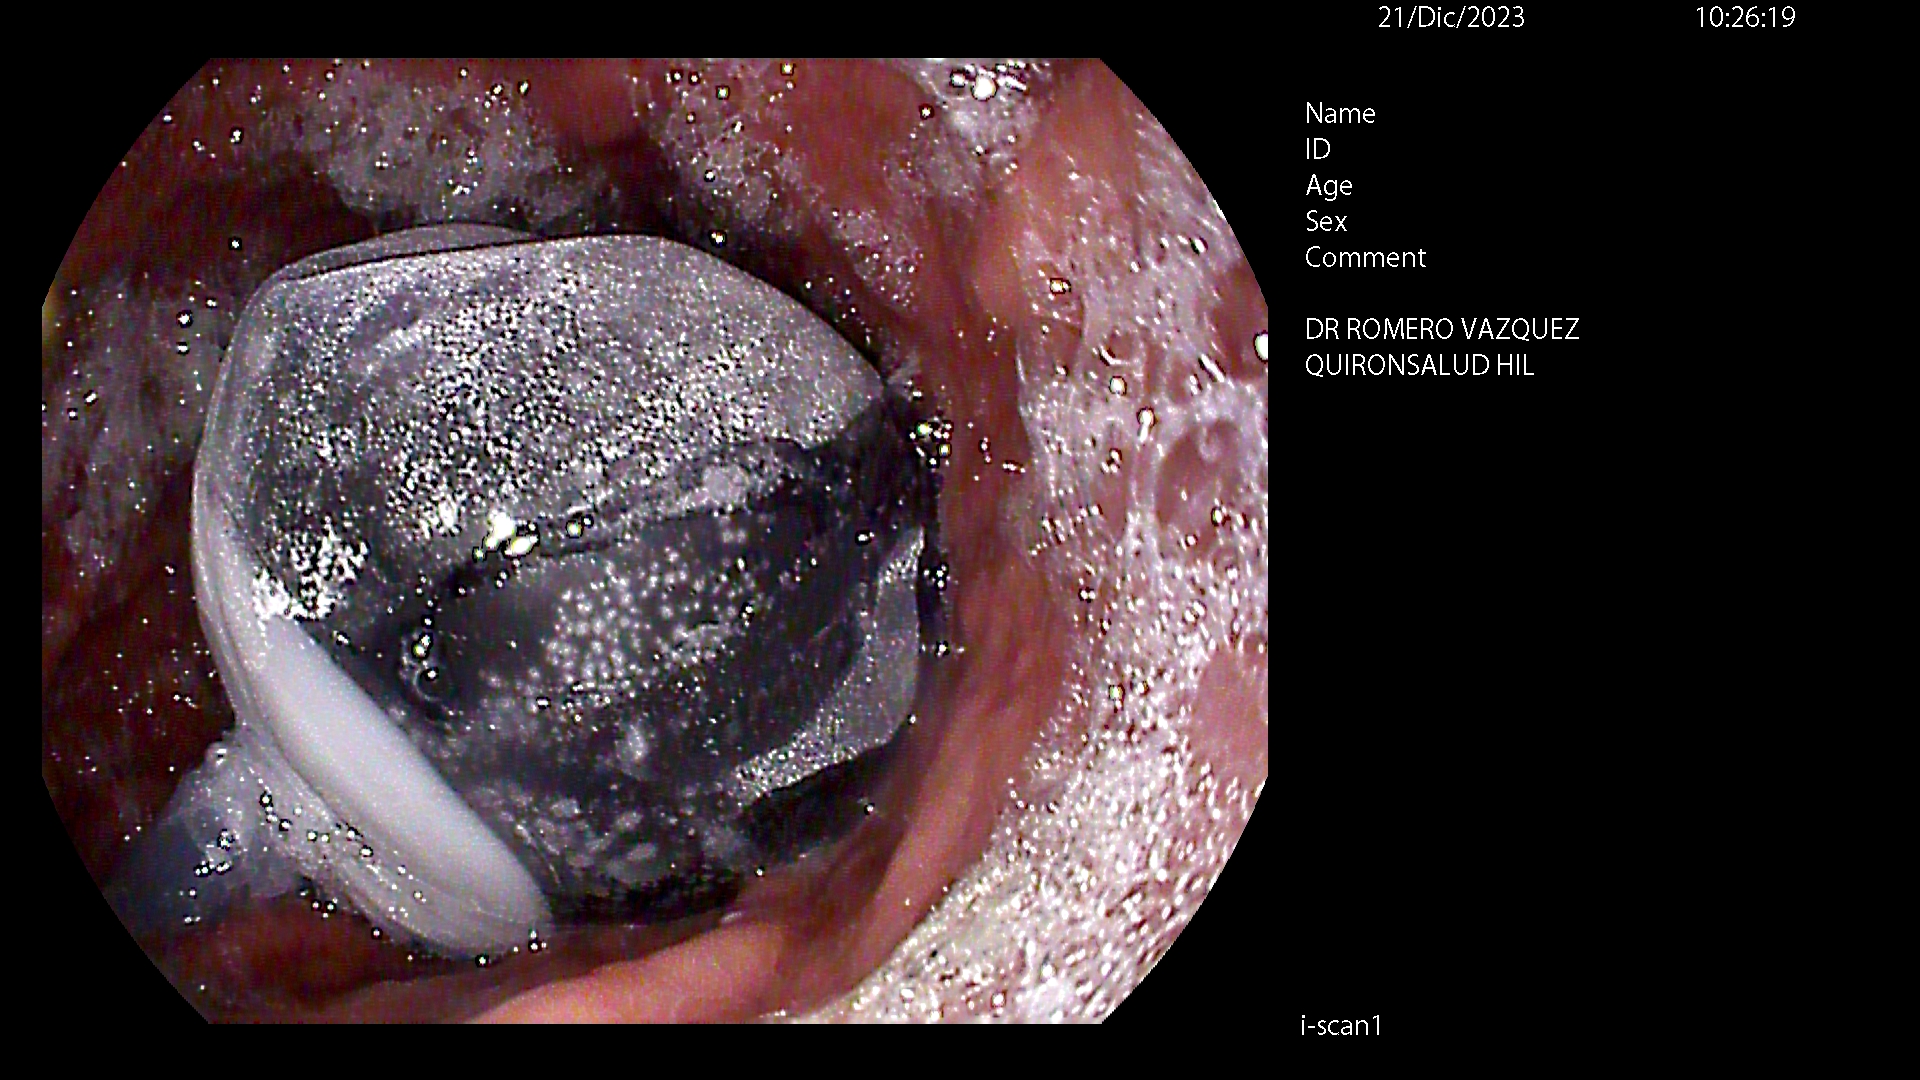

BALÓN INTRAGÁSTRICO

El balón intragástrico es un implante temporal de silicona, que rellenamos con suero, normalmente unos 500-600 cc, con un colorante (azul de metileno) para detectar cualquier posible anomalía futura (pérdida de contenido o rotura), una vez se aloja en el estómago y ocupa una parte importante del mismo. Esto genera dos mecanismos clave para aumentar la saciedad y por ello, perder peso:

- Ocupación de espacio: El dispositivo se aloja libremente en el estómago y genera ya de por sí una sensación de saciedad, ya que tiene entre 10 y 12 cm de diámetro.

Su colocación se realiza en la mayoría de las ocasiones por gastroscopia con sedación profunda administrada y controlada por anestesista, siendo una técnica ambulatoria (no precisa ingreso hospitalario) y su retirada, tras haber cumplido su función a los 6-12 meses, dependiendo de cada caso concreto, por gastroscopia con intubación y anestesista general, para minimizar los posibles inconveniente inherentes a la técnica, igualmente de forma ambulatoria.